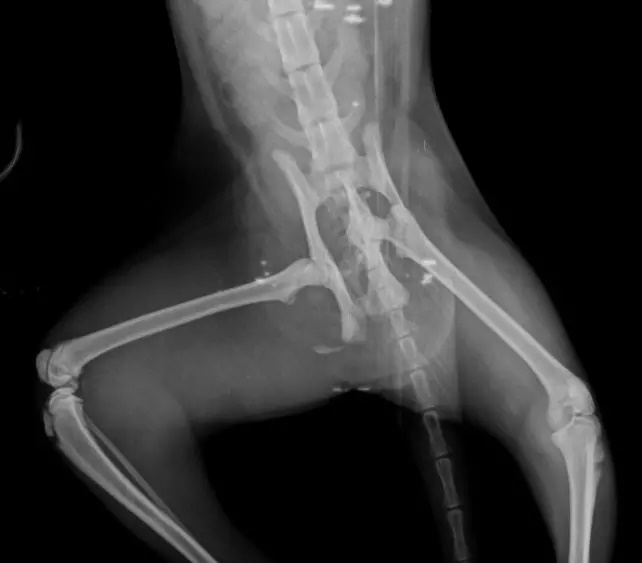

A jovem então pediu ajuda aos internautas e uma vaquinha foi feita para custear o tratamento da felina, que foi diagnosticada com uma fratura na bacia. O orçamento do procedimento ficou em R$ 2 mil.